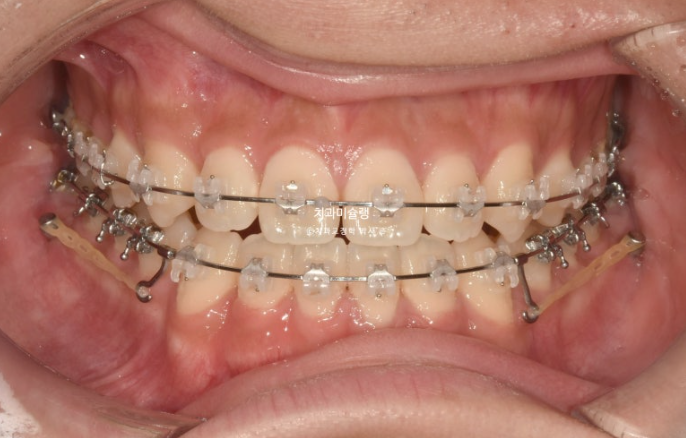

24.06

치료시작 1년째 모습입니다.

이때까지는 월 1회 꾸준히 내원했으나 이 시점 군입대를 하게 되셨습니다.

입대 후 3-4개월에 한번씩 내원하면서 치료를 이어갔습니다.

드디어 25년 말 치료를 마무리 했습니다.

중심선은 정확히 맞으며 개방교합은 충분히 해소되었습니다.

반대교합은 개선되었고 교합관계는 1급을 달성

치료 도중 군입대를 하면서 치료가 지연되어 토탈 기간은 2년 6개월 걸렸습니다.